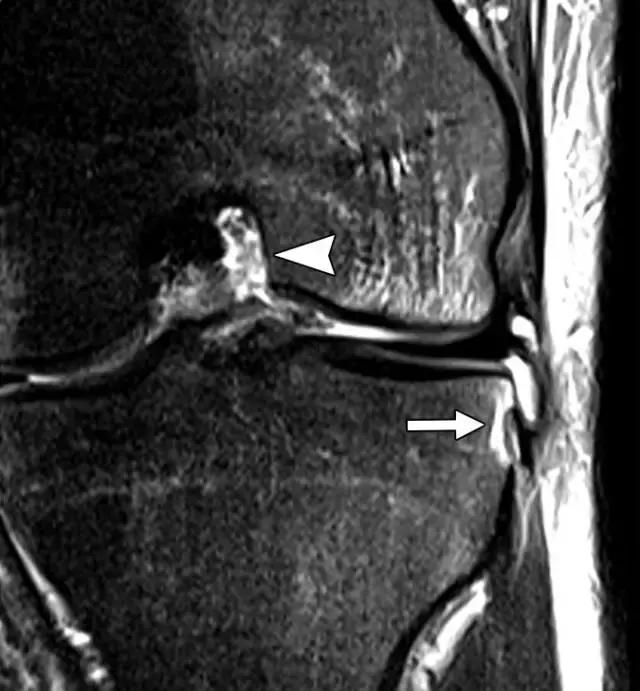

反向Segond骨折,是内侧胫骨平台的撕脱骨折,它是后交叉韧带严重受损的标志。这种骨折中的放射学检查结果与经典Segond骨折相似,只是反向骨折涉及胫骨近端的内侧(图6A)。据认为是由于内侧副韧带的深部荚膜组分的撕脱引起的(图6B),并且经常与内侧副韧带的严重损伤和相邻内侧半月板的周边损伤有关。

图6B,冠状脂肪抑制T2加权MR图像显示内侧胫骨平台内有明显的骨髓水肿,与内侧副韧带深部囊膜组分相关的反向Segond撕脱性骨折(箭头)。